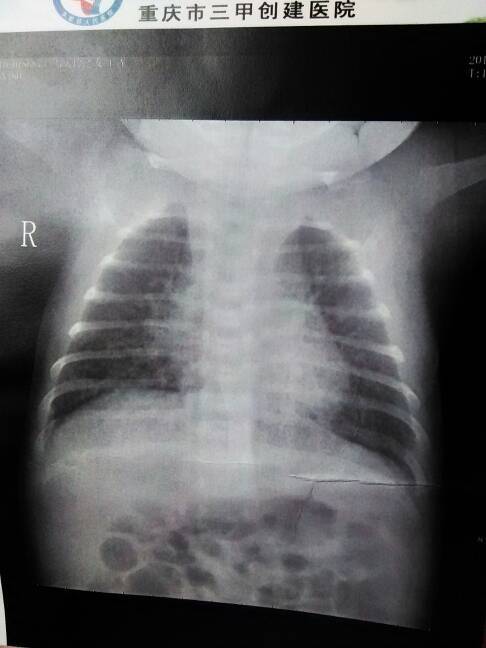

谁看得懂的,能帮我看看严重吗? 谁看得懂的,能帮我看看严重吗? 点击展开 ∩何必。 2015-02-26 15:54 为您推荐: 其他回答 看不懂,, 从零开始_Gm7A 2015-02-26 16:15 看不懂,, 陌路了 2015-02-26 15:58 相关问题 谁看的懂,要医生解答,帮我看看 谁帮我看看刚做的 胎儿B超单???我看不懂谢谢! 谁帮我看看刚做的 胎儿B超单???我看不懂谢谢!